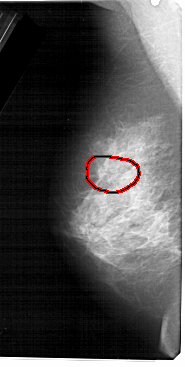

A_1474_1.LEFT_CC

LEFT_CC LINES 5161 PIXELS_PER_LINE 2326 BITS_PER_PIXEL 12 RESOLUTION 43.5 OVERLAY

FILE: A_1474_1.LEFT_MLO.OVERLAY

TOTAL_ABNORMALITIES 1

ABNORMALITY 1

LESION_TYPE CALCIFICATION TYPE PLEOMORPHIC DISTRIBUTION CLUSTERED

ASSESSMENT 4

SUBTLETY 2

PATHOLOGY BENIGN

TOTAL_OUTLINES 2